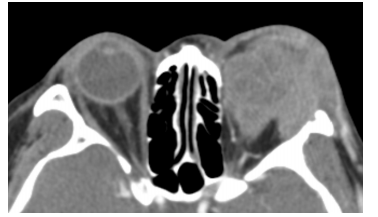

患者全身情况尚可,未见其他病变。眼部检查:右眼视力1.0,外眼和眼底检查未见异常;左眼视力指数/20 cm,眼球突出并向鼻下方移位,眼球突出度9 mm,眼球上转不能,内、外、下转受限严重,眼球运动受限,上眼睑高度红肿且有压痛,睑裂闭合不全,结膜高度充血水肿,角膜上皮有点片状灰白色混浊,虹膜正常,瞳孔反射(+),晶状体透明,眼底窥不清。左眼眶外上缘可触及质地较硬的肿物、约呈2 cm × 3 cm,边界不清,有压痛;眶压(++) (图1)。彩色超声波检查显示左眼眶外上方占位性病变,约呈3.08 cm × 1.81 cm,形态不规则,边界不清晰,内回声不均匀,有丰富血流信号,眼球壁受压明显。复查眼眶CT,显示左眼眶泪腺增大,眼眶内不规则团块影,边界欠清,内部密度不均,增强后可见均匀强化,邻近外侧眶骨壁有虫蚀状缺损,眼球受压(图2)。当地MRI显示,眶外上泪腺区椭圆形占位,T1WI为中低信号,T2WI为中高信号(图3)。结合患者的临床表现和天津市眼科医院CT检查结果,考虑为左眼眶部泪腺区占位性病变,不能排除恶性肿瘤。2007年10月12日,患者于全身麻醉下行左眼眶肿物切除术。术中发现眼眶上方充满灰白色肿物,无明显包膜,并侵及提上睑肌和眶上神经。

20230626161555_8529.png

图2 横轴位CT图像显示左眼眶内不规则团块影,侵及邻近软组织和外侧骨壁

Figure 2 Axial CT demonstrating irregular mass involving soft tissue and bone in the left orbit